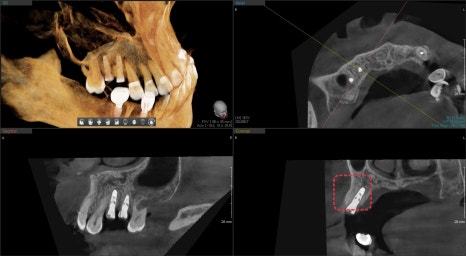

사진에 표시된 부분이 과거에 신경치료가 되어있었고

주변으로 염증이 생겨 치아를 지지해 주는 뼈가 흡수되어

치아 동요도가 관찰되었습니다.

발치 후 임플란트 즉시 식립을 해야 하지만

화살표로 표시된 부분이 염증으로 인해 흡수되어

임플란트를 식립하더라도 주변 뼈가 없어

노출이 될 수밖에 없는 상태였습니다.